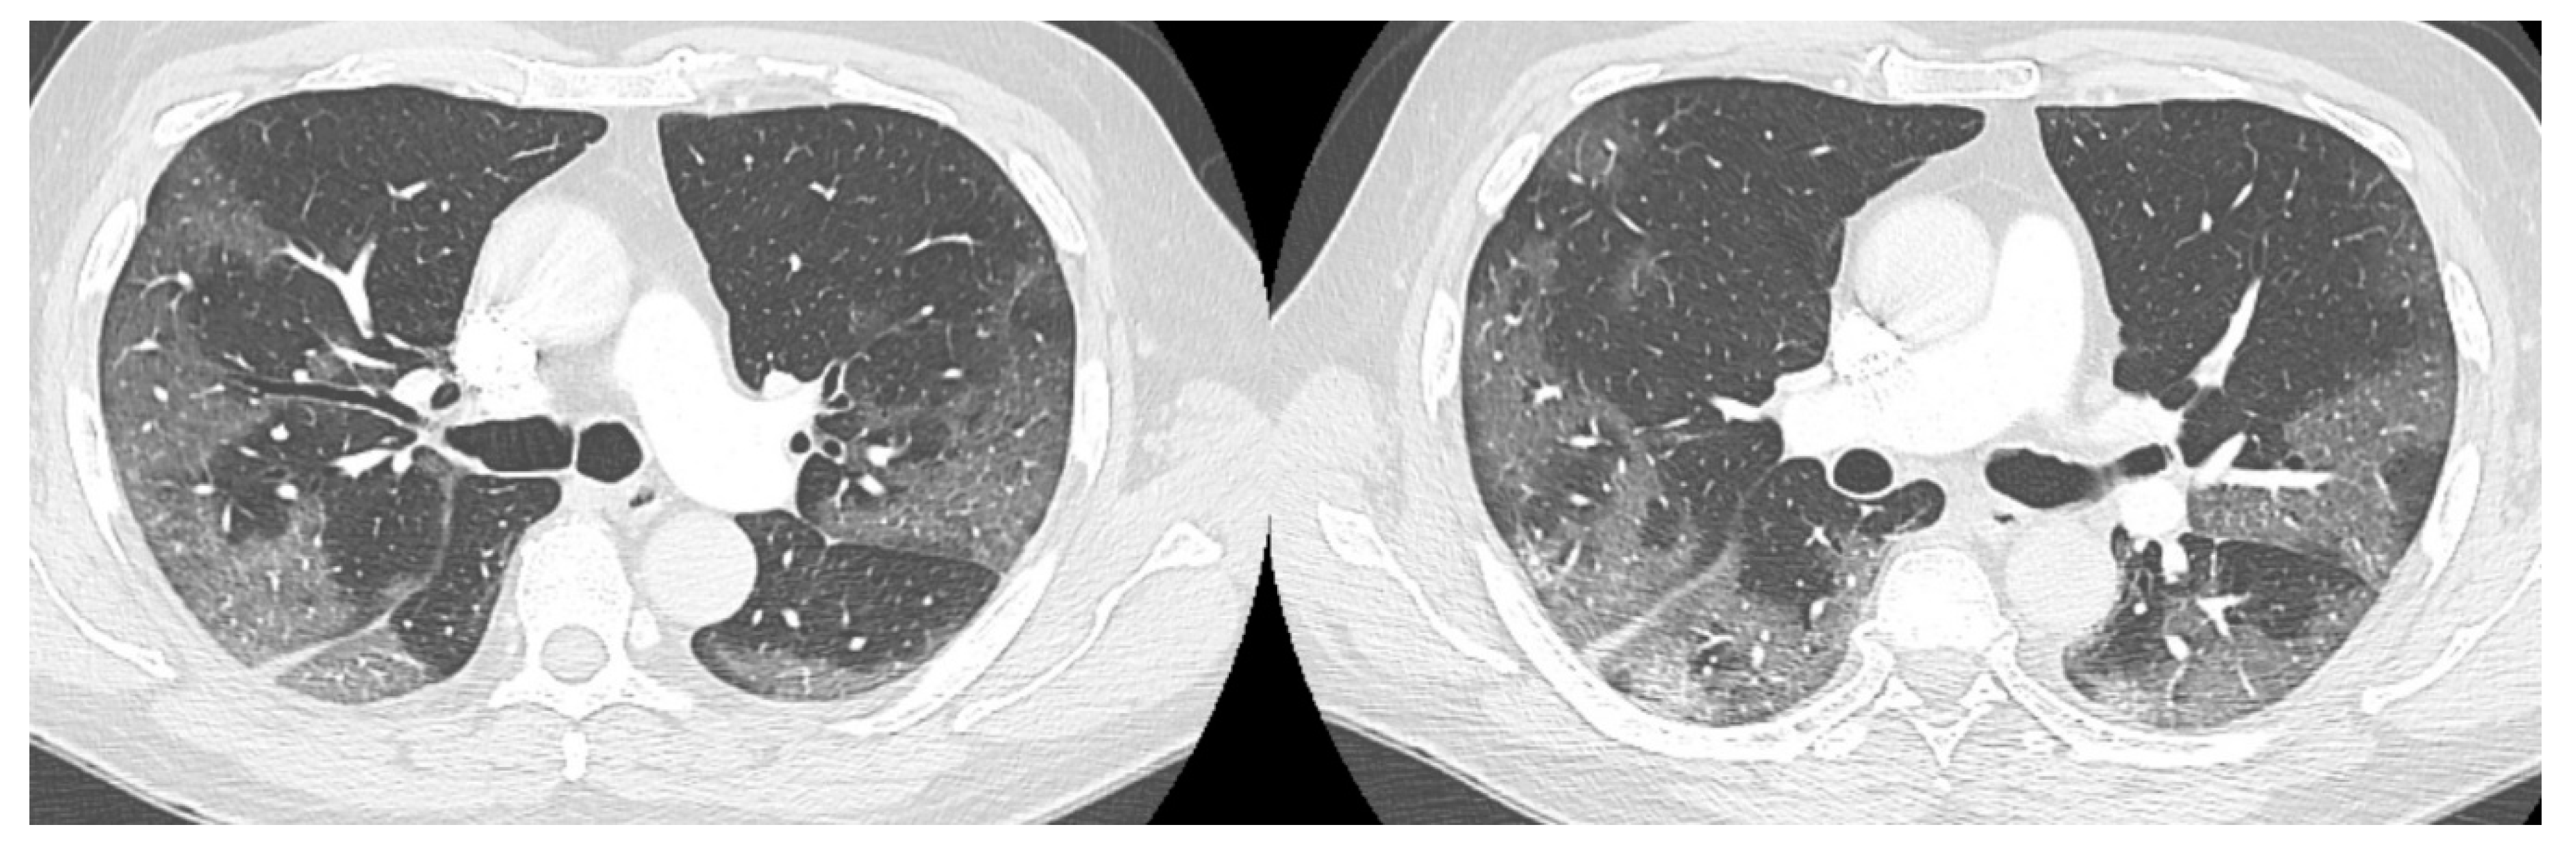

On day 22 from admission on a control HRCT was noted massive pneumopericardium in the absence of related symptoms (Figure 4). A new EKG was performed with absence of significant voltage reduction and showed sinus rhythm at HR 70 bpm. Atrioventricular conduction with PR 200 msec. Intraventricular conduction within the limits. (Figure 2B).

Figure 4. HRTC performed on day 22 from admission with evidence of massive pneumopericardium (red arrows) and severe presence of gas inside the pericardial sac (blue arrow). Detail of HRTC performed on day 22 show evidence of pneumopericardium (red arrow) and the severe presence of gas in the pericardium (blue arrow).